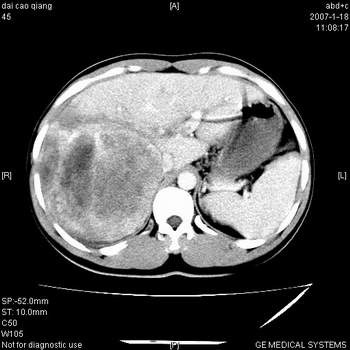

典型的肝右叶巨块型肝癌破裂、门脉瘤栓形成。

肝右叶巨大不均匀低密度肿块,前缘有假包膜,增强明显的呈快进快出表现,门脉右支有癌栓,病人虽然年轻但还是首先考虑肝右叶巨块形肝癌,病人血象高只能说有合并感染。不支持肝脓肿。

巨块型肝癌并门静脉右支癌栓

肝右叶巨块型肝癌破裂、门脉瘤栓形成。

肝右叶巨块型肝癌,伴瘤栓形成,肿瘤有包膜,可见动静脉短路。